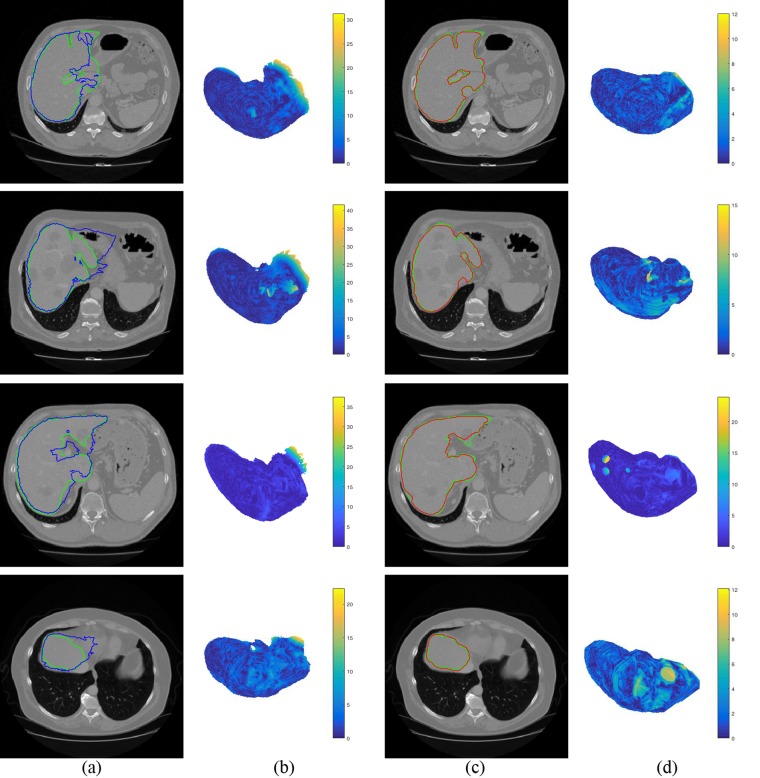

As can be seen in the 5th row of Table 2, initial shape of liver is far from final segmentation. Figure 8 shows the initial and final segmentation results with four difficult cases. The first row in Fig. 8a,c show that intensities of stomach and liver are almost same. MAS depending on intensity only can be applied to reach most of the target boundary, except the edges intersecting with two organs. After using multi-dimensional graph cut, the maximal distance to target boundary decreases from 32.32 mm to 12.04 mm (see the first row in Fig. 8b,d). The second row in Fig. 8a,c shows that there are some tumors in this CT image. This difficulty leads to 41.63 mm of the maximal distance to target boundary on initialization stage. After the initial shape is adapted, the maximal distance is decreased to 15.08 mm (see the second row in Fig. 8b,d). The third row in Fig. 8a,c shows that separating the sharp structures and the vessel is challenge. The maximal distance through coarse-to-fine segmentation decreases from 37.48 mm to 26.83 mm (see the third row in Fig. 8b,d). It can be observed from the fourth row of Fig. 8a,c that the boundary between liver and heart is hard to be distinguished. The maximal distance to target boundary is 11.98 mm on final segmentation, as well as that of initialization is 27.28 mm (see the fourth row in Fig. 8b,d).

Figure 8.

Liver initial and final segmentation results with four difficult cases. The ground truth is shown in green curves. (a) Initial segmentation (blue curves). (b) Surface distance between initial segmentation to ground truth. (c) Final segmentation (red curves). (d) Surface distance between final segmentation to ground truth.